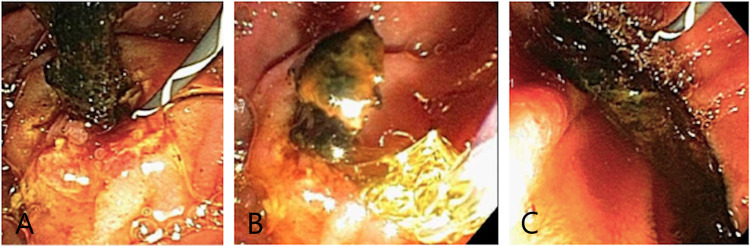

ERCP confirmed a distal linear filling defect within the lower CBD (Figure 2). Interestingly, there was CBD dilation without intrahepatic duct dilation (Figure 3). A sphincterotomy and balloon sphincteroplasty were performed. The linear bile duct stone in the shape of a bile duct cast was extracted using balloon sweep. There was mild oozing from his sphincterotomy, and hence his bile duct was stented given the need for the resumption of anticoagulation. A bile duct aspirate grew Staphylococcus epidermidis. After the procedure, his condition was found to be good with improvement in his liver enzymes. His antibiotics were deescalated to oral medications and his diet was advanced. His acute cholecystitis was managed with antibiotics. General surgery reviewed his case and offered an outpatient cholecystectomy.

A repeat outpatient ERCP was performed for stent removal. During this exam, his stents and further bile duct casts were removed. However, the second ERCP was indicative of significant intrahepatic ductal disease (Figure 4). He was evaluated by hepatology and diagnosed with SSC-CIP. Primary sclerosing cholangitis, congestive hepatopathy, and other causes of secondary sclerosing cholangitis were excluded.

Cases of acalculous cholecystitis in the context of COVID-19 have been reported in the literature [ref. 5]. One case report has also described secondary sclerosing cholangitis in a critically ill patient precipitated by COVID-19 [ref. 6]. It is postulated that SSC-CIP may be secondary to both bile duct ischemia and altered bile composition [ref. 7,ref. 8]. Bile duct epithelium is supplied by the hepatic arterial branches and the delicate peribiliary plexus [ref. 9]. Bile duct ischemia leads to canaliculicular dysfunction and cholestasis [ref. 10]. As described in a previous retrospective review, our case demonstrated biliary casts and pruning of the biliary tree, without any damage to the CBD [ref. 11]. What is unique in this case is that the patient’s biliary casts caused cholangitis and his SSC-CIP was diagnosed on ERCP and not magnetic resonance cholangiopancreatography (MRCP) [ref. 11]. If ERCP is performed for SSC-CIP, three patterns can be seen on the cholangiogram. The first, as seen in this patient, is biliary casts. Bile duct casts are characteristic of SSC-CIP and are present in up to 87% of cases. The second is the loss of intrahepatic ducts secondary to destruction. The final pattern is a significant small duct drop-out with the cholangiogram resembling a pruned tree [ref. 11].